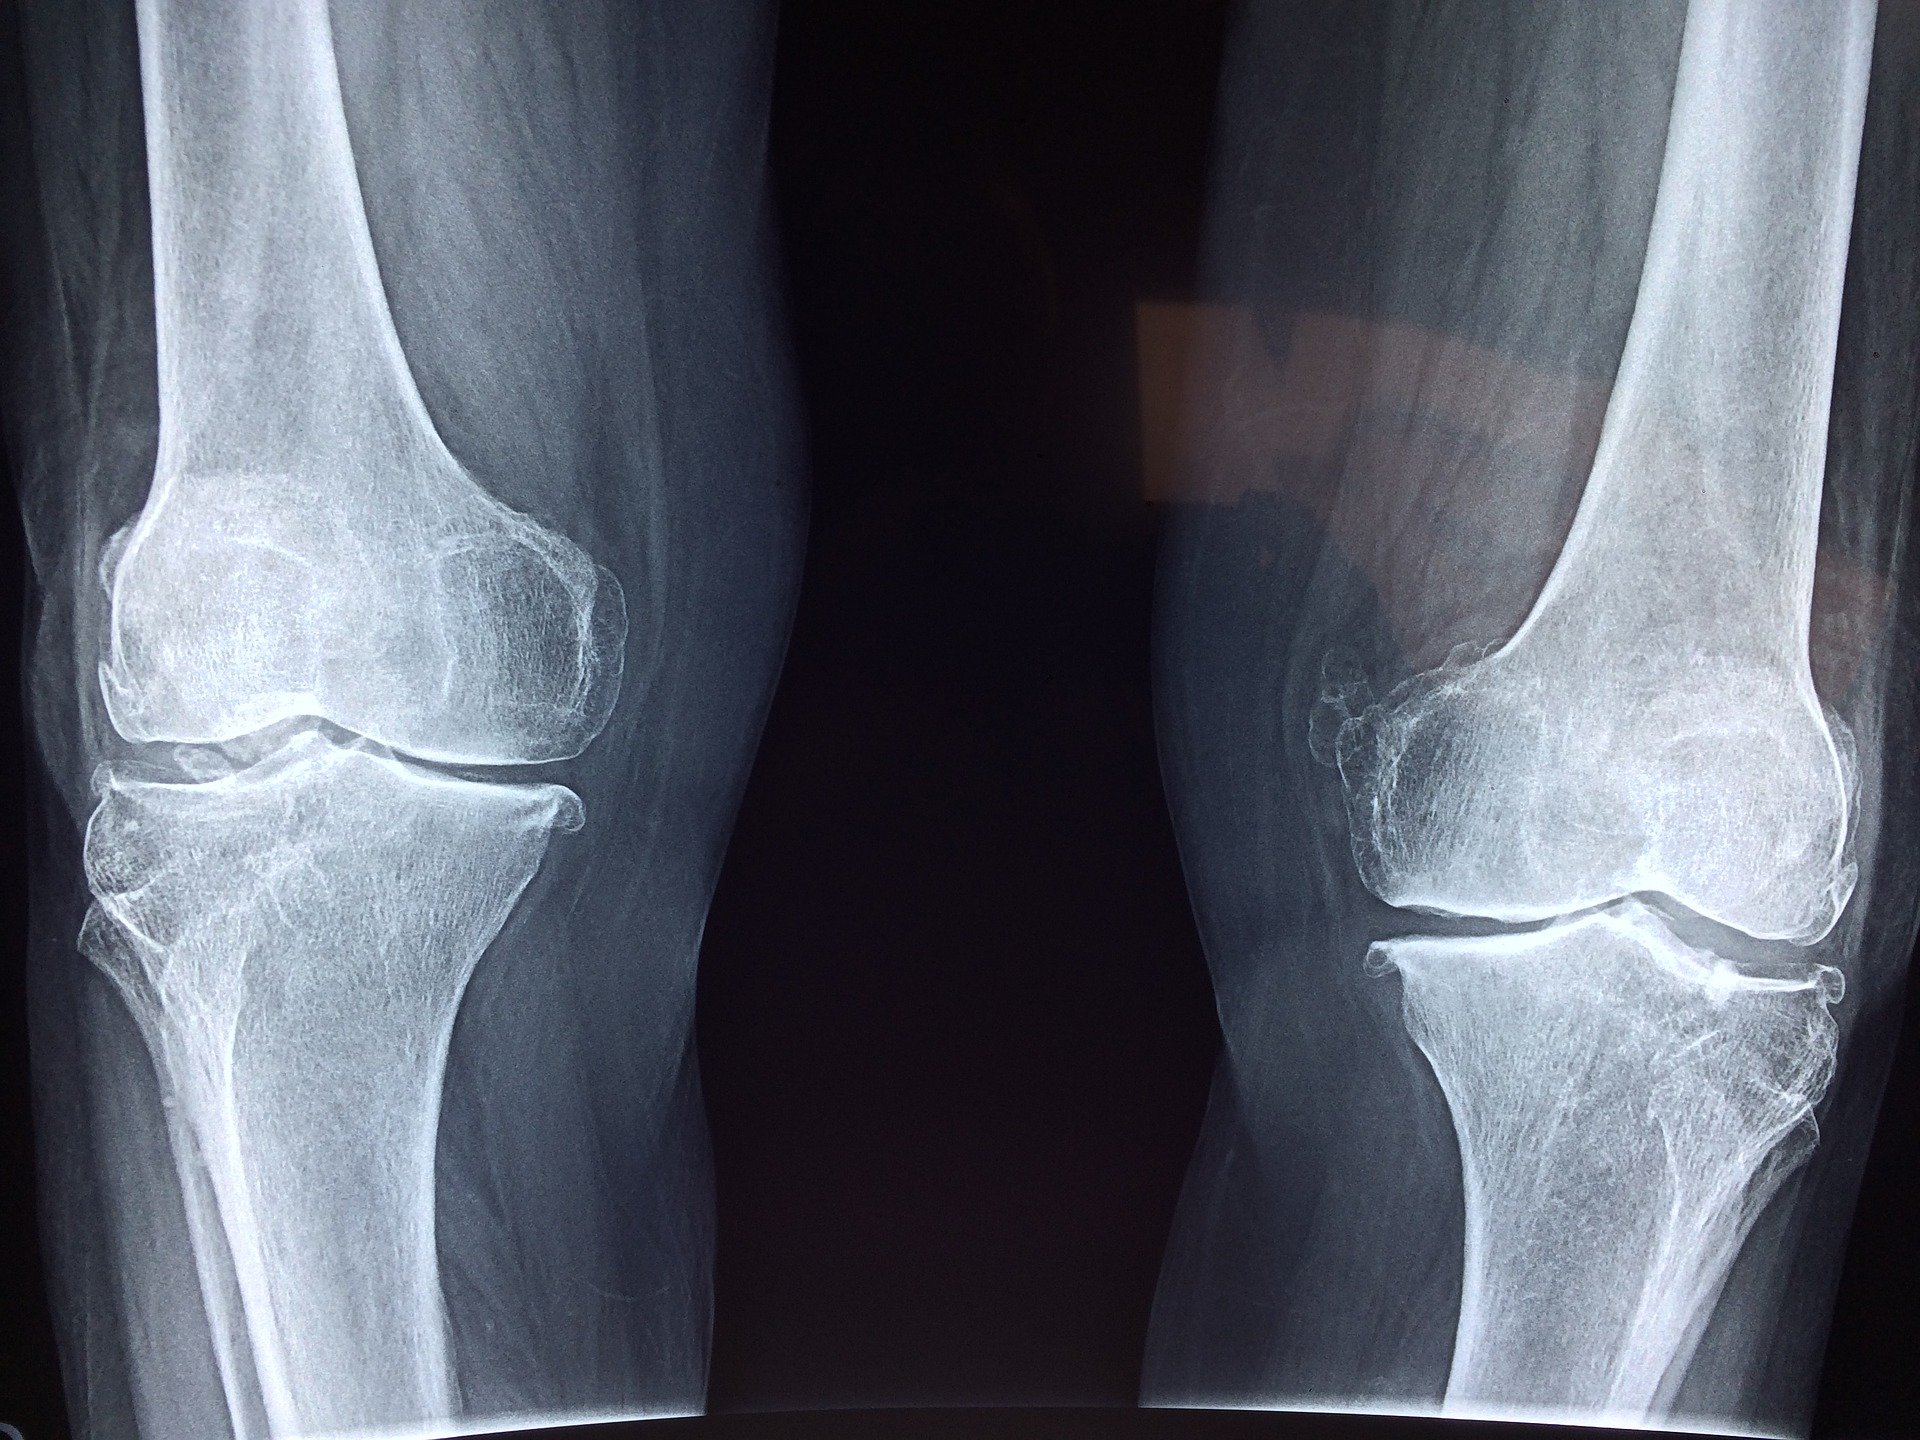

Wiadome jest, że ból i obrzęk kolana świadczą o problemie zdrowotnym. Dlatego tak ważne jest, aby wraz z zaostrzeniem objawów udać się do lekarza. Wcześniej można próbować niwelować symptomy domowymi sposobami. Specjalnie dla Ciebie zebraliśmy w jednym miejscu najlepsze sposoby na ból, obrzęk czy wodę w kolanie. Należy jednak pamiętać, że nic nie zastąpi profesjonalnej wizyty u lekarza.